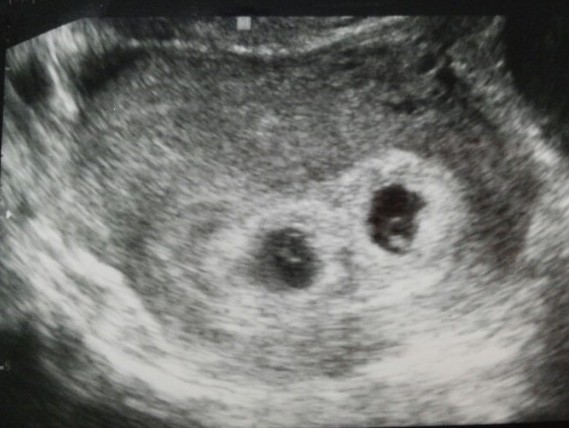

초음파 기계를 배에 가져다 대보니

하얀 점이

두개가 보였다.

여기...점 두개보이시죠

쌍둥이네요

여기에 쌍둥이 있데..

하얀점 두개...

쌍둥이래요..